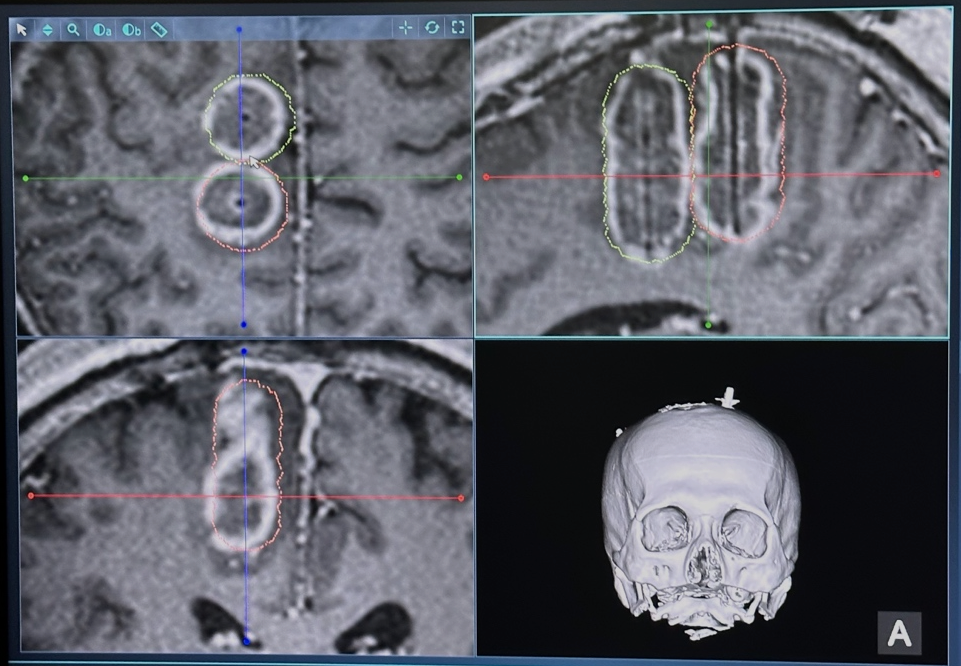

“这种技术简单说是使用具有精确制导能力的神经导航系统,将毫米级的光纤‘送’到肿瘤里,利用磁共振实时精准控制温度,对肿瘤进行激光消融。”周大彪说,应用这种技术,既可以避免开颅手术创伤过大且肿瘤无法完全切除、切除过程中可能影响大脑功能区等问题,经过与患者和家属充分沟通,患者决定采用这种治疗方案。

为了确保万无一失,医疗团队和工程技术人员团队一起,为王先生进行了充分的术前准备,通过任务态功能磁共振(t-fMRI)和纤维束成像(DTI)技术确定运动区和神经传导束的位置及与肿瘤的毗邻关系,反复讨论确定神经导航计划、不同剂量的双光纤消融,以及激光光纤置入路径和治疗靶点等。

手术当天,在医院的复合手术间,医疗团队通过神经导航精准定位后,通过颅骨上毫米级的小孔,按照计划路径将光纤准确置入肿瘤内部,在磁共振实时成像的监测下,按照计划对肿瘤进行消融,手术全过程不到2小时。